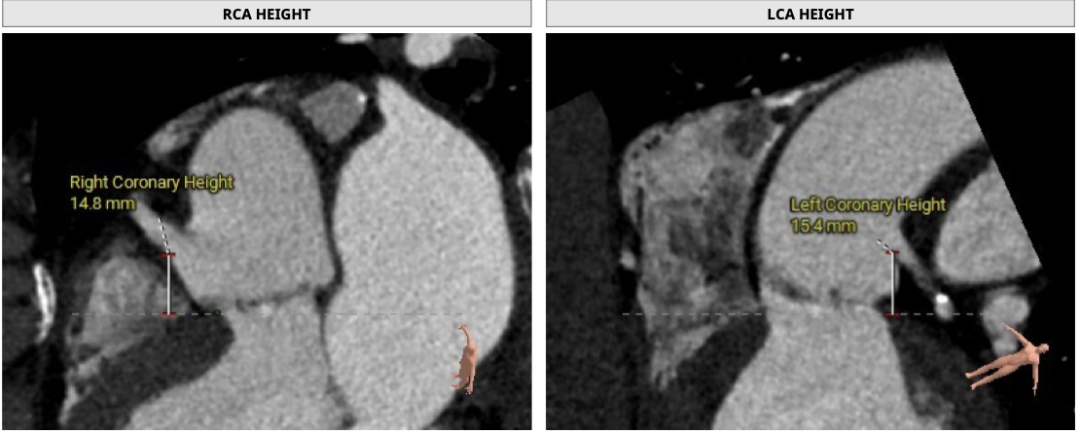

双侧冠脉开口高度可LCA:15.4mm,RCA:14.8mm,左右冠脉轻度钙化: